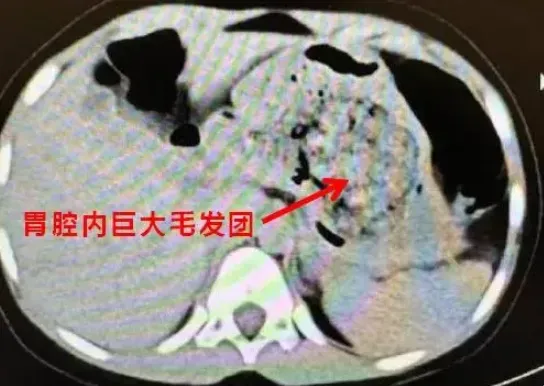

5歲女童腹痛難耐!醫從胃裡取出「一大坨毛髮」 確診為「長髮公主症候群」